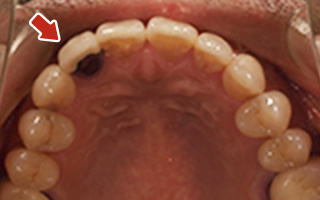

Before

After

| 45歳 男性 | 医療関係者紹介 |

|---|---|

| 主訴 | 右前歯が取れた(右上2) |

| 処置内容 |

1本インプラント埋入+再生療法 抜歯即時埋入⇒抜歯を行い、同時にインプラント埋入(即時埋入) |

| 治療費用 | 上顎: 約40万円(税込) |

| 治療期間 | 約11ヶ月 |

| リスク | 上部構造物、仮歯の破折、術後の腫れ(3日)、人工歯根脱落リスクがあります |